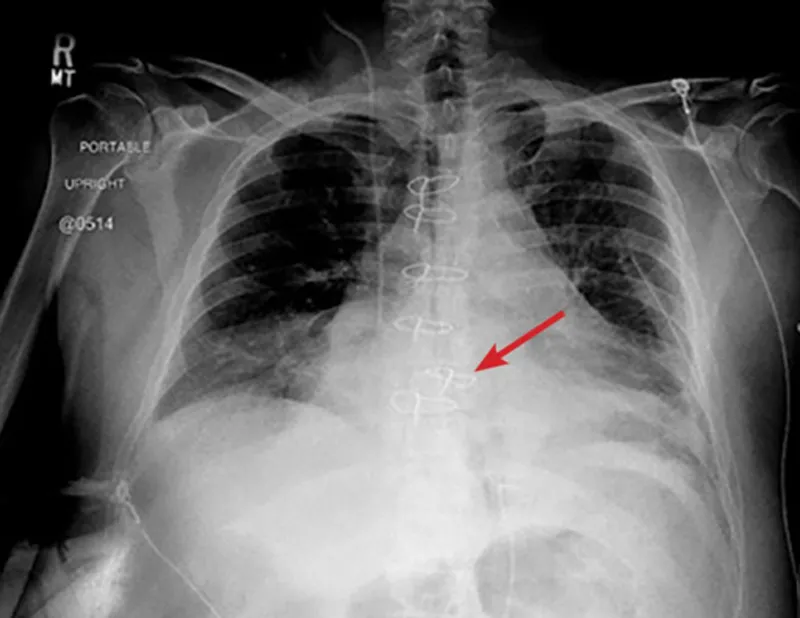

- Sternal Dehiscence & Instability:

- Clinical: Sternal pain, clicking, palpable gap, instability.

- CXR: Wire fracture/migration, sternal separation > 2-3 mm.

- CT: Defines extent, associated collections, early osteomyelitis.